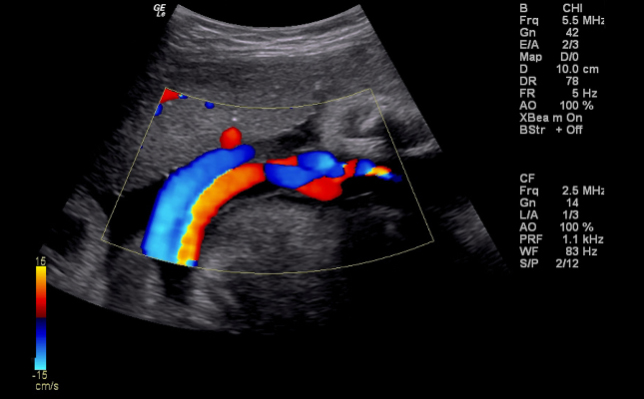

2018/11/20 健康・ダイエット 【心電図、そして…】勤務中、突如動悸が激しくなり、呼吸が苦しい状況に!? 田原 総二郎 ( 五反田エリア / 店舗運営スタッフ ) 上司心拍数病院早期発見不安ドクター心電図原因不明動悸呼吸が苦しい深夜勤務心臓バクバク救急外来波打つグラフ線脈拍1分間で120回心臓エコー生きた心地スコープ吸って吐いてモニターホルター心電図心臓の動き数値チェックMRI不摂生 冒頭から少し暗い話になりますが、つい数日前、深夜勤務中に突如動悸が激しくなり、呼吸が苦しい状況になりました。「このままではヤバい」と思い、自分で病院に電話をして、症状を伝え、今から行くことを告げました。 あまり大事にはしたくなかったので、上司を呼び出しコソッと病院に行って来る旨を伝えました。なんとか自力で行けそうでしたが、心配だからと、上司が病院まで送ってくれました。 目次1 到着2 心臓エコー3 ホルター心電図 到着 心臓はバクバクの状態でしたが、なんとか病院に到着しました。 事前に連絡を入れておいたので、救急外来に到着するとすぐに病室に通され、ベットに横になるよう指示されました。 横になると、「今から心電図をとりますので」と、看護師さんが3人で私の身体に手際よくペタペタと線のついたコードを張り始めました。すべてを張り終えると、「しばらくじっとしててくださいね」と看護師さんに言われ、大人しく横になっていました。 しばらくして、波打つグラフ線のようなものがプリントアウトされ、ドクターがやってきました。その表を見ながら、今度はドクターが私の手首に指を当て脈拍を測りました。 結果は、1分間で120回とかなり早い心拍数です。「緊張しているせいかもしれないので、後でもう一度測ります」とのことで、一度待合室に戻り、再度呼ばれるまで待機します。 そこで、待つこと30分・・・声が掛かり、また病室へ。30分休憩したことで心拍数も落ち着いているはずと思い、ドクターが私の脈拍を測りましたが、なんと30分の休憩があったにもかからわず、休憩前と同じ120回という数値。 これには、ドクターもどうしたものかと頭を悩ませ、「これから心臓のエコーをとります!」という流れに。私としては、「なんでもいいから早くなんとかしてくれ~!!」という気持ち。本当に生きた心地がしませんでした。 心臓エコー 「機械のある部屋に移るので、隣の病室へどうぞ」・・・そして、エコーの用意してある部屋へ。 「はい、ベットの上に横になってくださーい」と言われ、なすがままに。またペタペタとコードの付いたものを体に貼り付けました。 そして、スコープを当てながら「はい、吸ってくださーい、吐いてくださーい」を繰り返しながら、ドクターがモニターを見守ります。 結果的には、ドクターも「ん~?」と首をひねるばかりで原因がわからず。 ホルター心電図 結局のところその場では何もわからず、「ホルター心電図を付けて、心臓の動きを24時間見てみましょう」ということになりました。身体に機械を付けられ、翌日、数値をチェックすることに決まり、その日は病院を後にしました。 自分はこのままどうにかなってしまうのではないか・・・と、不安だらけで生きた心地がしません。 後日、MRI等を使って検査をすることに・・・早期発見とはいうものの、今までの不摂生を考えると不安しかありません。しかし、どんな結果であっても、真摯に受け止めようと思います。 この記事を書いた人 田原 総二郎 ( 五反田エリア/ 店舗運営スタッフ ) 将来は一人で海外生活を送りたいと考えており、大好きな海・酒・カラオケ三昧の毎日を送りたいと考えています!1日でも早く実現できるように日々奮闘しています。 田原総二郎の記事一覧へ 田原総二郎が書いた記事 2020/05/21 【ぶらり一人旅~御殿場編③~】『御殿場プレミアムアウトレット』で時間潰し 2020/03/27 【ぶらり一人旅~御殿場編②~】『さわやかハンバーグ』の待ち時間にビックリ!? 2020/03/03 【ぶらり一人旅~御殿場編①~】渋滞もなんのそのテンション上げて行ってきます 他にもこんな記事が読まれてます 2020/06/06 【お茶ダイエットの効果検証】ラーメンと一緒にお茶を飲んだ時の体重推移 2020/05/27 【マッサージ沼Part2】さまざまな種類のマッサージ屋さんをハシゴする!! 2020/05/15 【40代で人生初のシックスパック】トレーニングで使ってる器具と筋肉の追い込み方 2020/05/09 【痛風の次は糖尿病②】美味しいお酒を飲むために食生活を徹底改善!! 2020/04/17 【春バテに要注意!!】新生活は自律神経が乱れて体調を崩しやすくなる!? 2020/04/13 【虫歯ゼロを目指して③】ついに忌々しい親知らずとの別離の日がきた! 【15年振りの買い替え】パソコンが壊れたので格安PC買ってみました♪ 【魂を震わすホビー!】大人になった今だからこそ楽しめるミニ四駆!!